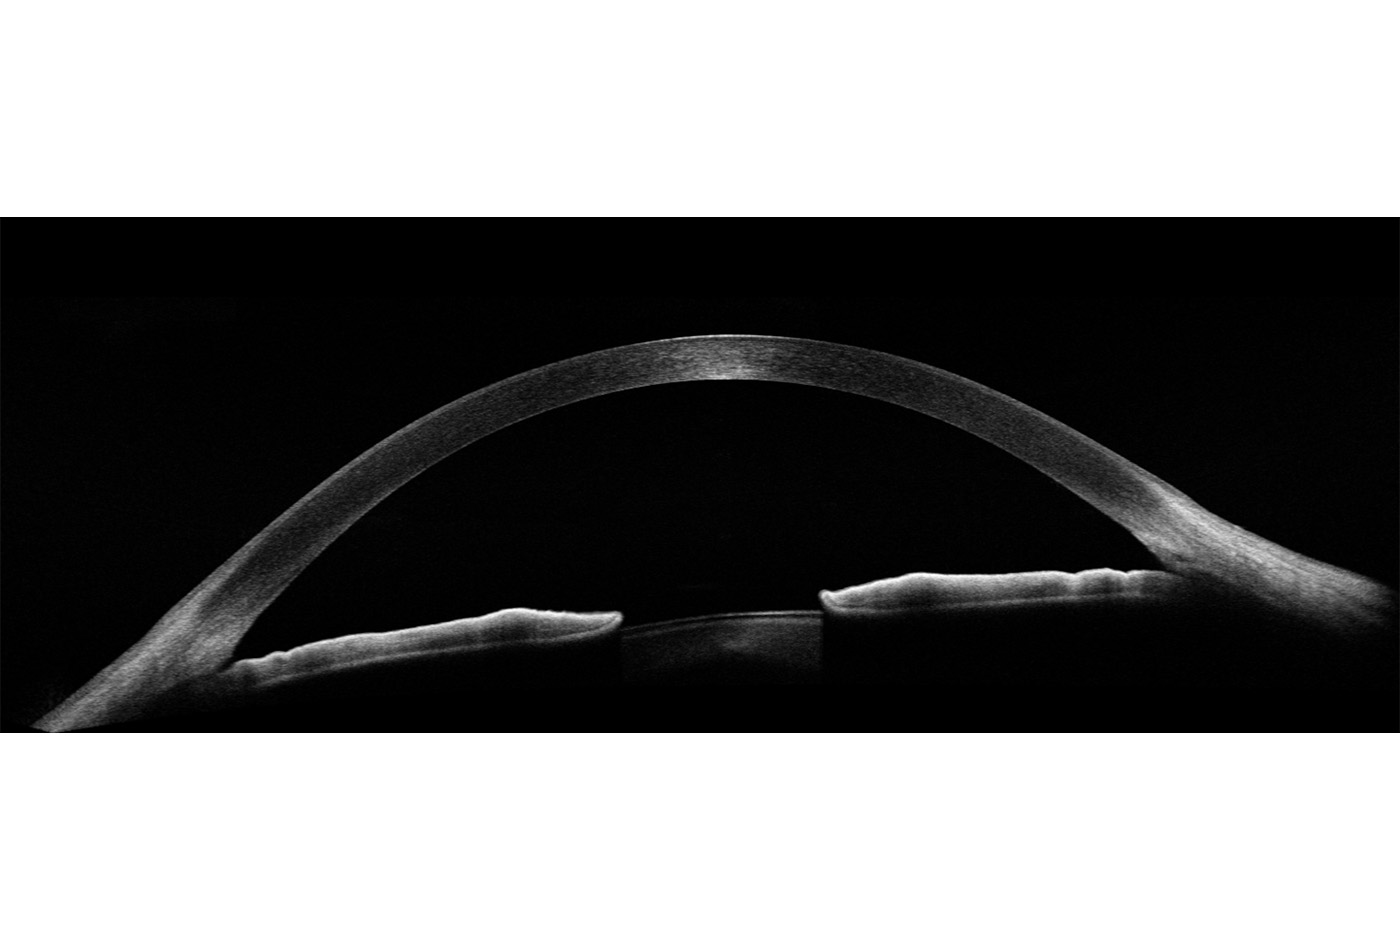

Vorderabschnitt:

- Integriertes Vorderabschnittsmodul (5 X 5mm)

- Autom. Pachymetrie

- Analyse des Kammerwinkels

Optionales Weitwinkelmodul (14 X 5mm):

- Darstellung des vollständigen vorderen Systems

- Messung zweier Kammerwinkel in einer Aufnahme

- Darstellung der Iris